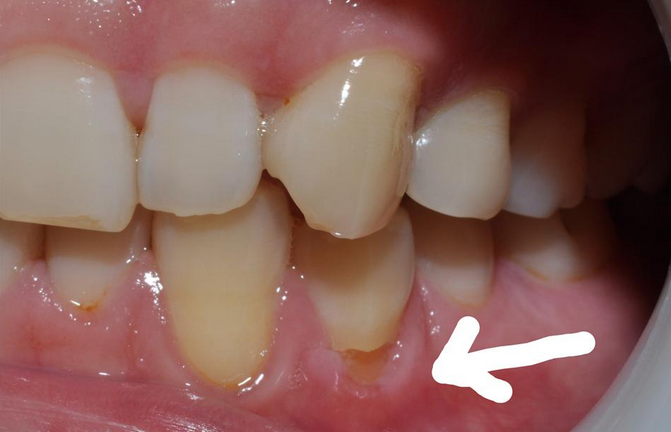

牙齒出現的「凹槽」,其實學術說法就是「楔狀缺損」;這個詞語雖然看上去有點難以理解,其實說白了就是朋友口中的:牙齒頸部上的一道「凹槽」。因為從側面看,這一道凹槽就是外側寬裏側窄,像是一個「楔子」的空隙。楔狀缺損的存在,就可能讓牙齒內部的牙本質更容易接受(甚至直接暴露)到來自外界(唾液、食物、空氣等)的冷熱刺激,甚至吸一口冷風都會感覺到從頭到腳的酸痛感。

另一個跟我們日常生活密切相關的原因,就是用力橫刷牙的不良習慣。刷牙的幅度、力度過大、方向不對,都可能加重楔狀缺損。尤其是刷牙的幅度,很多人總是「磨刀霍霍」向牙齒,就像磨菜刀一樣。力量大,且一個來回半口牙都刷到了。這是一種不好的習慣,雖說牙刷比牙齒軟的多,但是耐不住「水滴石穿」,堅硬的牙齒也會被磨出一道槽來。這道槽往往就處在牙頸部,也就是牙齒和牙齦相近的位置。並且,因為刷牙導致的「楔狀缺損」還有一種非常典型的表現:它們更容易出現在左側的牙齒。